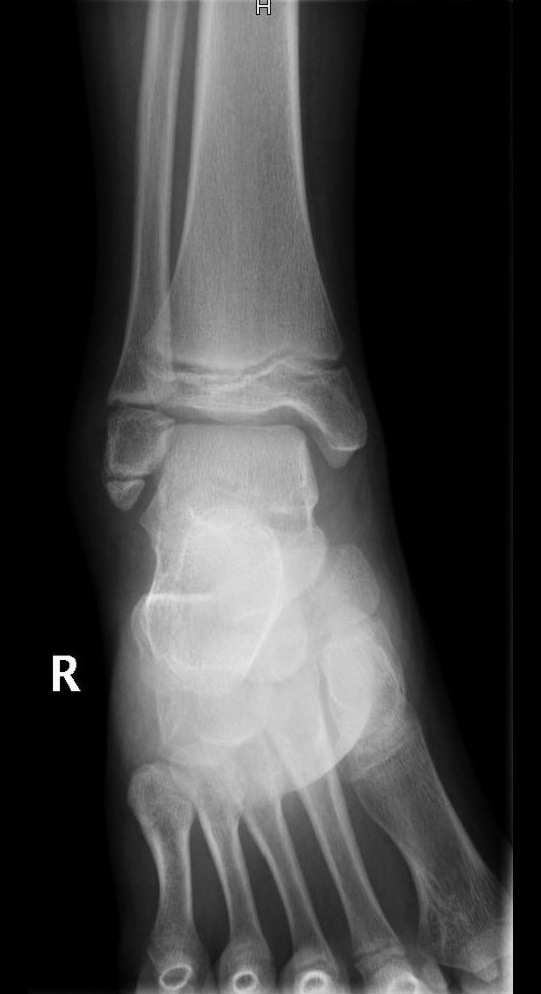

Niña de 11 años de edad sin antecedentes de interés que acude a Urgencias por dolor a nivel del maléolo externo del miembro inferior derecho tras un movimiento anómalo del pie con inversión del tobillo hace 2 días. Asocia tumefacción e impotencia funcional leves. Le han administrado analgesia en el domicilio sin mejoría. A la exploración, presenta tumefacción y dolor selectivo a la palpación del maléolo externo y los ligamentos peroneoastragalinos anterior y posterior.